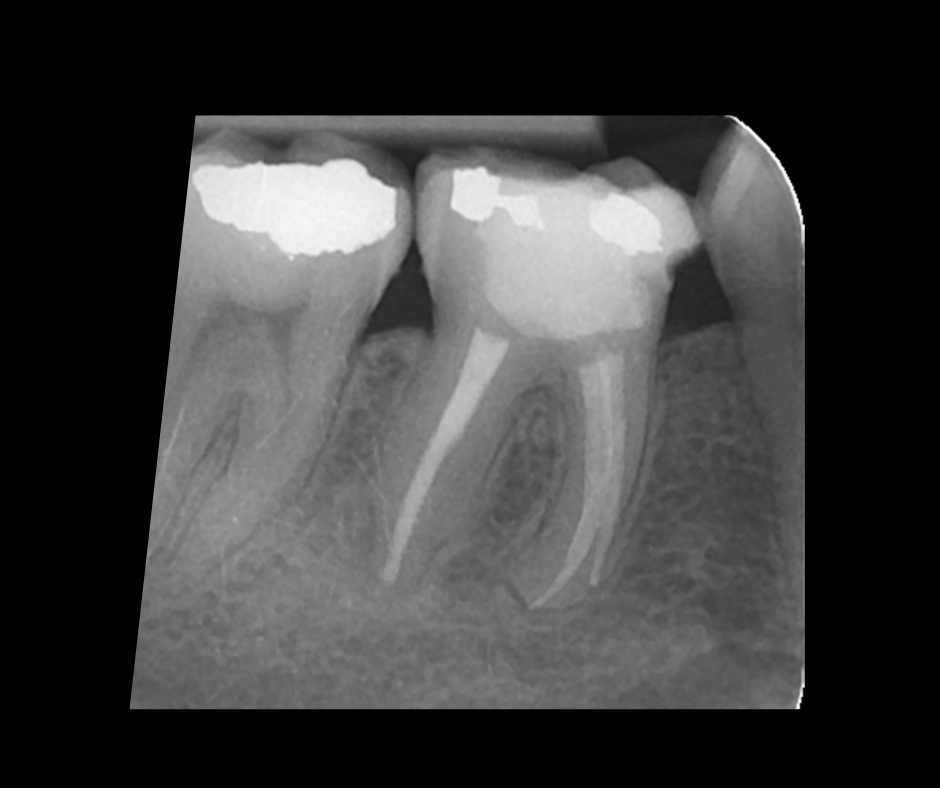

This course focuses on modern single-file endodontic systems, guiding participants through diagnosis, case assessment, access cavity design, canal location, root canal system preparation, and obturation techniques.

• To acknowledge the updates in endodontic irrigation and methods of improving irrigation efficacy within the root canal system

• To gain confidence in endodontic obturation and develop an understanding of various obturation techniques and methods of developing predictable, reproducible endodontic obturation

14.00 – 16.00 – Contemporary NiTi 2: Mechanical Preparation and Update on Irrigation

16.20 – 18.00 – Obturation and Orifice seal